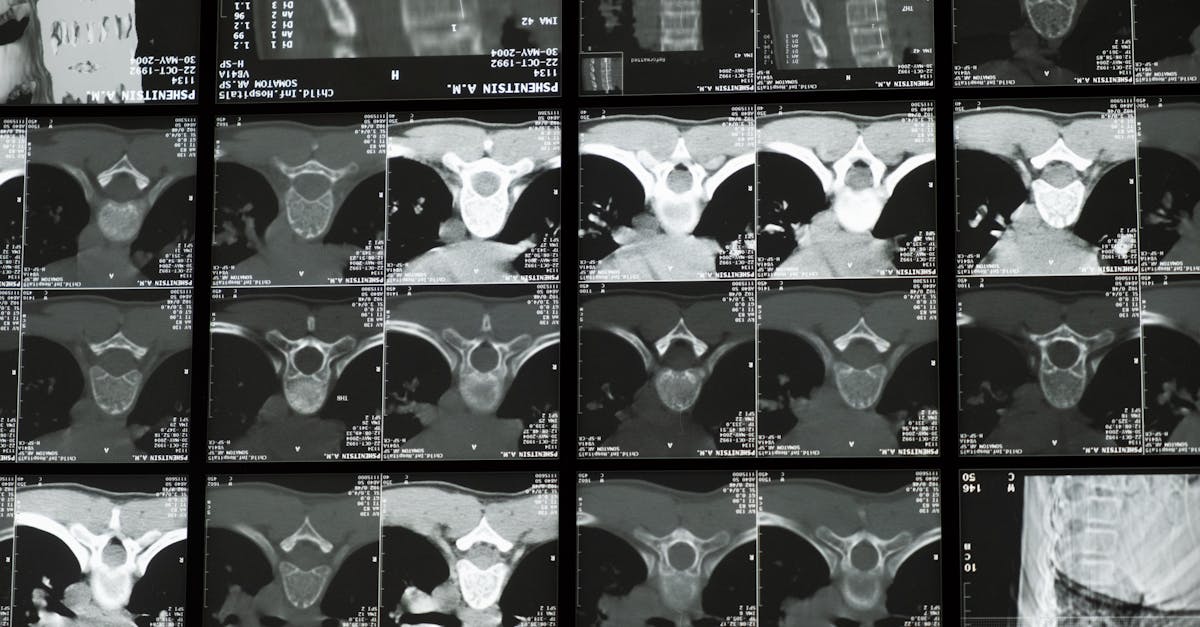

Commençons par le cas précis qui a déclenché l’alerte : une jeune femme s’est présentée à son rendez-vous d’IRM en laissant malencontreusement un plug anal contenant un noyau métallique à l’intérieur de son corps. Cet objet, conçu majoritairement en silicone mais intégrant un composant ferromagnétique, a interagi violemment avec le champ magnétique de l’appareil IRM. La technologie de l’IRM repose sur des impulsions magnétiques très puissantes capables de générer des images radiologiques nettes et détaillées.

Comprendre la technologie IRM et pourquoi elle amplifie les risques liés au métal

L’IRM utilise des champs magnétiques puissants associés à des ondes radio pour produire des images transversales précises des organes et tissus. Contrairement aux rayons X ou scanners, l’IRM ne fait pas appel à la radiation ionisante, ce qui en fait un choix de prédilection pour un large éventail d’examens médicaux. Cependant, cette technologie médicale est basée sur un principe physique qui interagit directement avec les propriétés magnétiques des matériaux.

Le professeur Adam Taylor, expert en anatomie humaine, souligne que la vitesse à laquelle de petits objets ferromagnétiques se déplacent à l’intérieur du champ magnétique peut atteindre jusqu’à 60 km/h. Dans le cas du sextoy oublié, ce déplacement a approché la vitesse du son, accentuant considérablement les risques physiques aux conséquences dramatiques.

Le lien entre la technologie IRM et la physique des matériaux métalliques justifie ainsi pleinement un protocole rigoureux de sécurité.